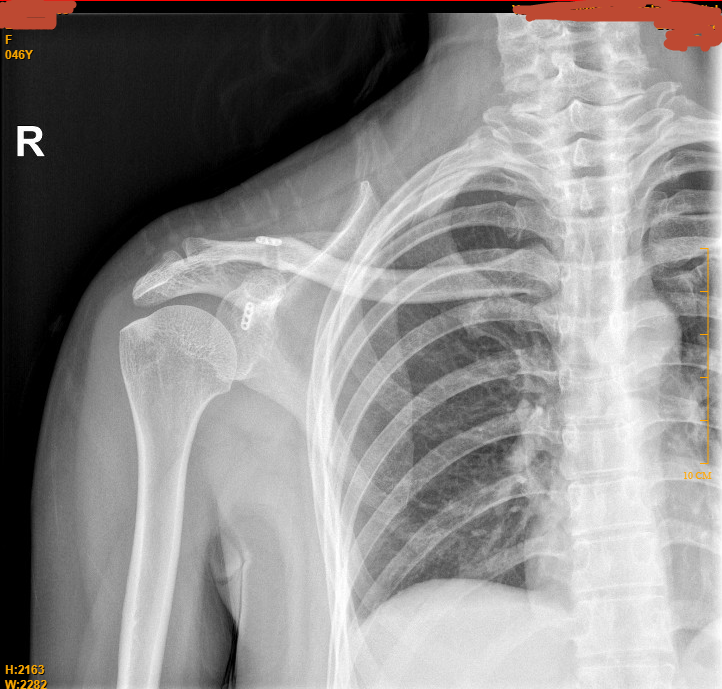

双侧肩关节负重对比片:右锁骨远端上翘,右侧肩锁关节间隙较左侧明显增宽 。右侧肩锁关节脱位。

结合辅助检查:双侧肩关节负重对比片:右锁骨远端上翘,右侧肩锁关节间隙较左侧明显增宽 。右侧肩锁关节脱位。故右侧肩锁关节脱位诊断明确。

本例患者有明确的右侧肩关节外伤病史,根据双侧肩锁关节负重对比片可以明确为三度的肩锁关节脱位,故需要进行情况复位内固定手术治疗。以往的手术内固定一般选择锁骨钩钢板,本例患者选择进行绊钢板内固定术。相对于传统的锁骨钩钢板的方案,绊钢板内固定术能够直接观察和处理肩锁关节的脱位情况,确保复位准确、固定牢靠。